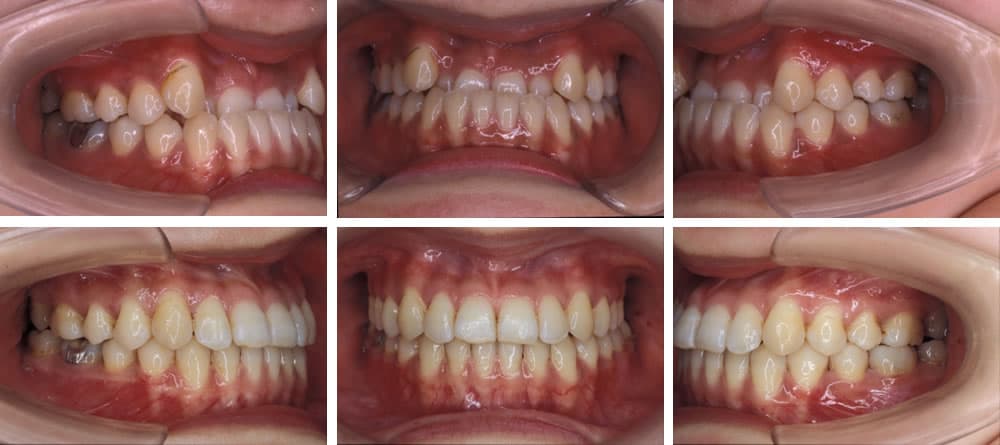

矯正治療を推奨する代表的な歯並びについて

叢生(八重歯など)

叢生は歯が様々な向きに生え、ばらばらな状態の歯並びです。歯が重なった部分のケアが難しいため、虫歯や歯周病リスクが高くなります。また、見た目も悪くコンプレックスに感じる方も少なくありません。

上顎前突(出っ歯)

上顎前突は上の顎や歯が前方に出ている状態の歯並びです。口腔内が乾燥しやすいため、唾液の殺菌作用が低下し、虫歯や歯周病リスクが高くなります。また、見た目が悪いことや前歯を損傷しやすいことも特徴です。

下顎前突(受け口)

下顎前突は下の顎や歯が前方に出ている状態の歯並びです。前歯の咬み合わせが悪く、奥歯の使用頻度が高くなるため、奥歯の喪失リスクが高くなります。また、顎骨にも負担がかかるため、顎関節症になりやすいという特徴があります。

開咬(オープンバイト)

開咬は上下の歯を咬み合わせた際、前歯が咬み合わずに隙間ができてしまう歯並びです。正しい咀嚼ができないため、胃腸などの消化器官に負担がかかります。また、口腔内が乾燥しやすく、唾液の殺菌作用が低下するため、虫歯・歯周病リスクが高くなります。

過蓋咬合(ディープバイト)

過蓋咬合は上下の歯を咬み合わせた際、下の歯が見えなくなるほど上の歯の咬み合わせが深い歯並びです。下の歯で上の歯茎を傷つけたり、正しい咀嚼ができないことで顎骨や胃腸に大きな負担がかかったりなど、様々な問題が懸念されます。

空隙歯列(すきっ歯)

空隙歯列は歯と歯の間が大きく開いた状態の歯並びです。食べ物が挟まりやすいため、虫歯や歯周病リスクが高くなります。また、見た目の問題や歯の間から空気が抜けることによる発音障害などが懸念されます。